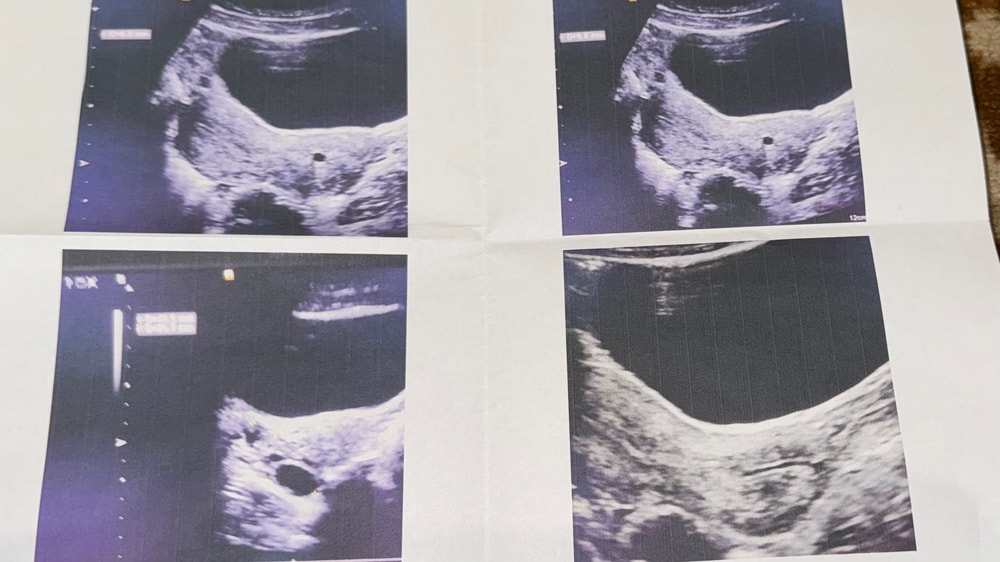

Шейная беременность или наботовая киста?

это «нечто» в шейке размером 6 мм напрягает и меня и врачей которые делали узи..

У меня было это что-то ) в шейке. Причем в беременный цикл нашли. Что было до сих пор не знаю, спутали с плодным яйцом. Слава богу это было не оно и плодные яйца позже появились в матке. То в шейке тогда так и осталось тоже размером 6мм. А потом исчезло и никто больше не видел 🤷🏼♀️

mom and baby, а моей представьте.. я на работе пришла на узи с положительным хгч. Они видят «плодное яйцо» в шейке, плодное маленькое 2мм в матке, два желтых тела. И кладут срочно в больницу естественно. Там видят то же самое, жалоб нет, решают ждать несколько дней. Лежу, не знаю что и думать, долгожданная беременность. Через несколько дней узи повторяют - в матке первое яйцо выросло, второе появилось. В шейке как было 6мм так и осталось. Не растет- значит не ПЯ😁 выписали, все дальше было хорошо, никаких выделений, болей и прочего

VM,и у меня тоже похожая история. На первому узи поставили многоплодную беременность под вопросом, т.к. одно плодное яйцо было в матке, а одно якобы яйцо , еще видели в шейке. На втором узи сказали что в шейке это киста. А на последующих узи в шейке уже ничего не видели.